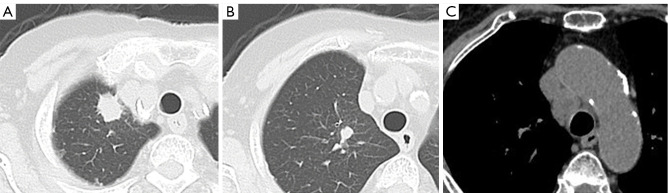

Case description: An 83-year-old woman with lung adenocarcinoma harboring MET exon 14 skipping mutation presented with right upper lobe nodules and bilateral mediastinal lymphadenopathy. The initial EBUS-TBNA yielded insufficient specimens for molecular testing. Subsequent EBUS-IFB and mediastinal cryobiopsy provided sufficient specimens for definitive diagnosis. Twenty-nine days after the procedure, computed tomography revealed rapid growth of the right upper lobe nodules and a tracheal mass at the biopsy site, consistent with NTS. Despite this complication, the patient demonstrated a marked response to tepotinib therapy, with significant regression of both the lung and tracheal lesions.